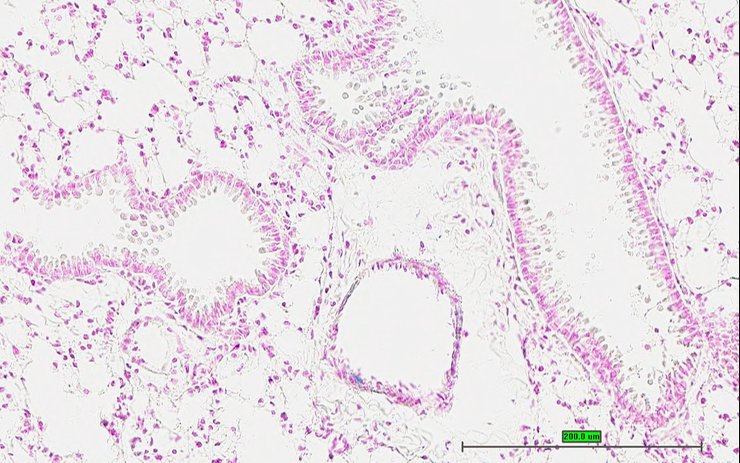

TS28: lung Present UC Davis_1876914

Specimen UC Davis_1876915: postnatal adult; Fosbtm1b(KOMP)Wtsi/Fosb+ (more )